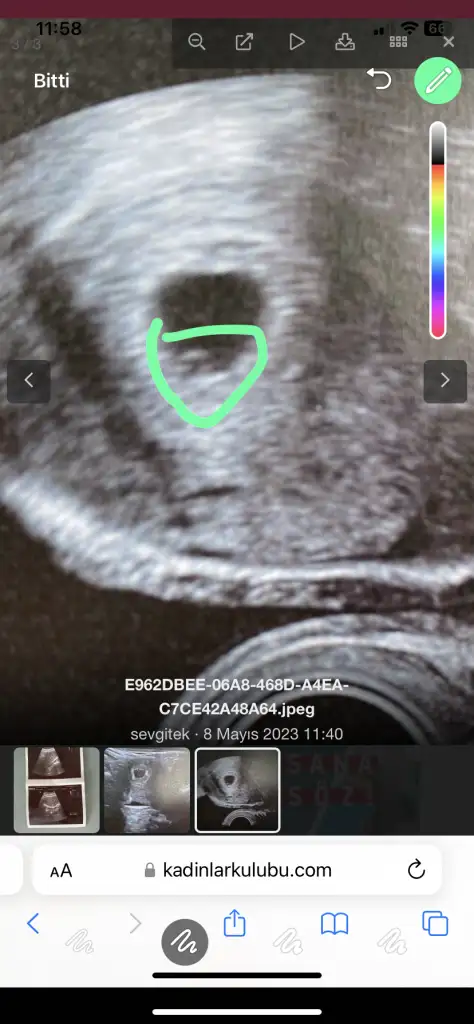

bak o işaretledigim alandakş yuvarlak var ya o yolk sac o olustuysa bebek de var daha minik burda ondan gözükmemiş haftaya kesin görürsün yolk sac bebek olusmadan olusmaz zTen

Eklentiler

• A9BEA4A6-D53B-4324-B8E4-7E70B357D2C6.webp

A9BEA4A6-D53B-4324-B8E4-7E70B357D2C6.webp

27,7 KB · Görüntüleme: 491

görürsün canım merak etme bebek olmadan yolk olusmaz ilk haftalarda yolk plesenta görevi görür seninki bariz ortada yusyuvarlak ben bakınca direkt gördüm netten de bak sana attım seninki gibi yuvarlak ❤️ yolk varsa bebek de vardır merak etme